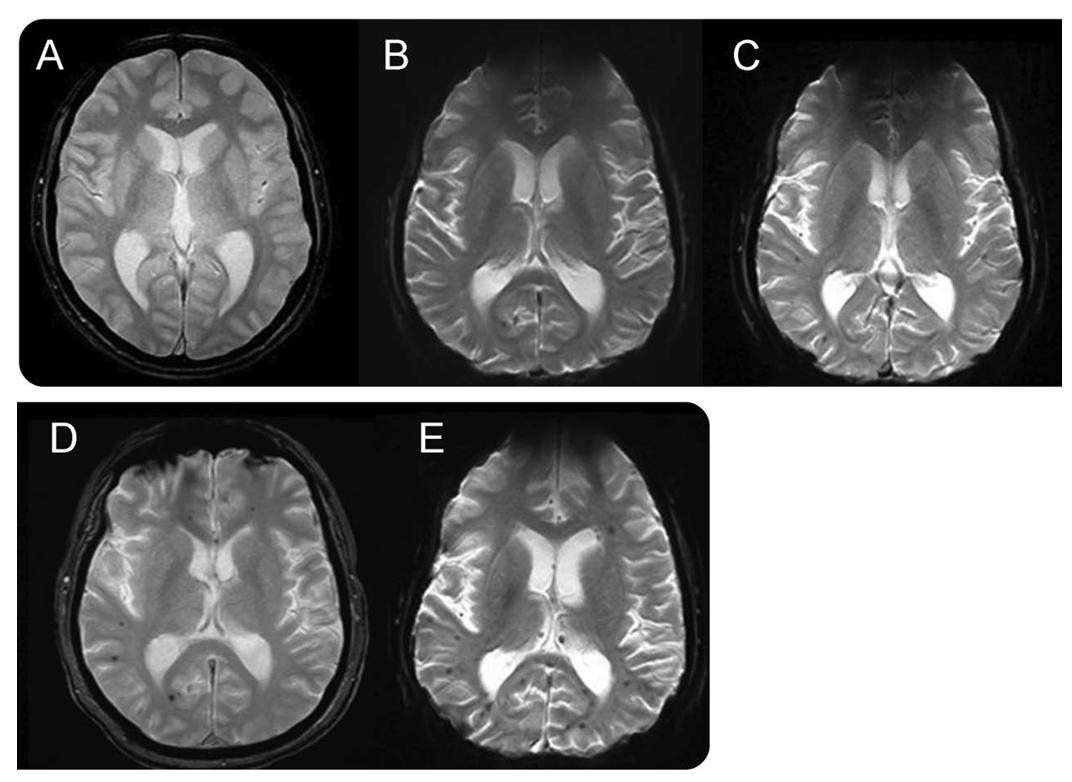

放疗 T2*WI示放疗前(A)、放疗后21个月(B)、放疗后33个月(C)、放疗后44个月(D)和放疗后62个月(E)。CMBs随时间的延长而增多。